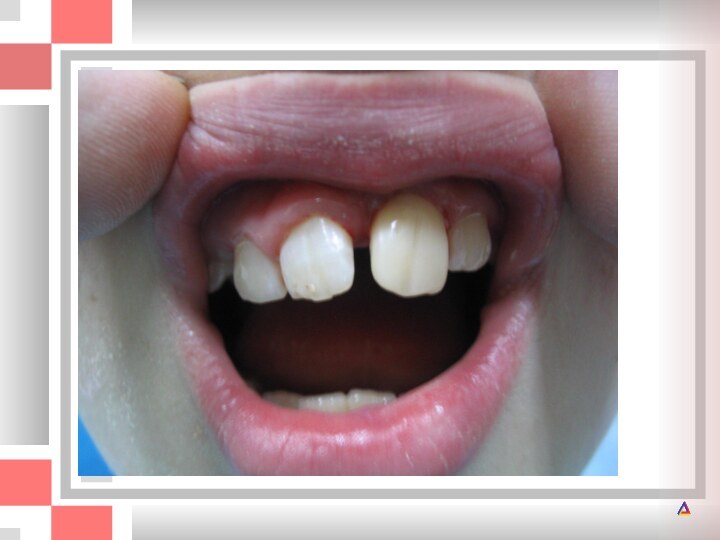

Год назад левый молочный центральный резец получил травму. После травмы зуб

После травмы зуб казался здоровым, однако впоследствии анкилозировался, что

не позволило ему полностью прорезаться.

Анкилоз постоянного центрального резца после травмы. Прорезывание резца прекратилось. Зуб следует удалить.